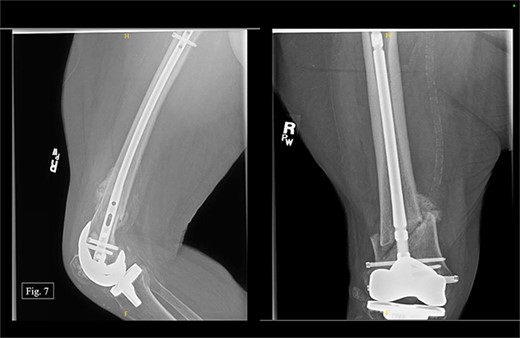

The patient was seen at Texas Tech Orthopedic Clinic 2 weeks after discharge from University Medical Center with no postoperative complications. In December 2022, 3 months after being treated on the right with a retrograde nail, the patient reported bilateral knee pain (5/10 on the left and 6/10 on the right). During the visit, AP and lateral right knee X-rays were taken (Fig. 7). She could ambulate with a walker during the visit and reported doing consistent physical therapy at home but no longer seeing a physical therapist.